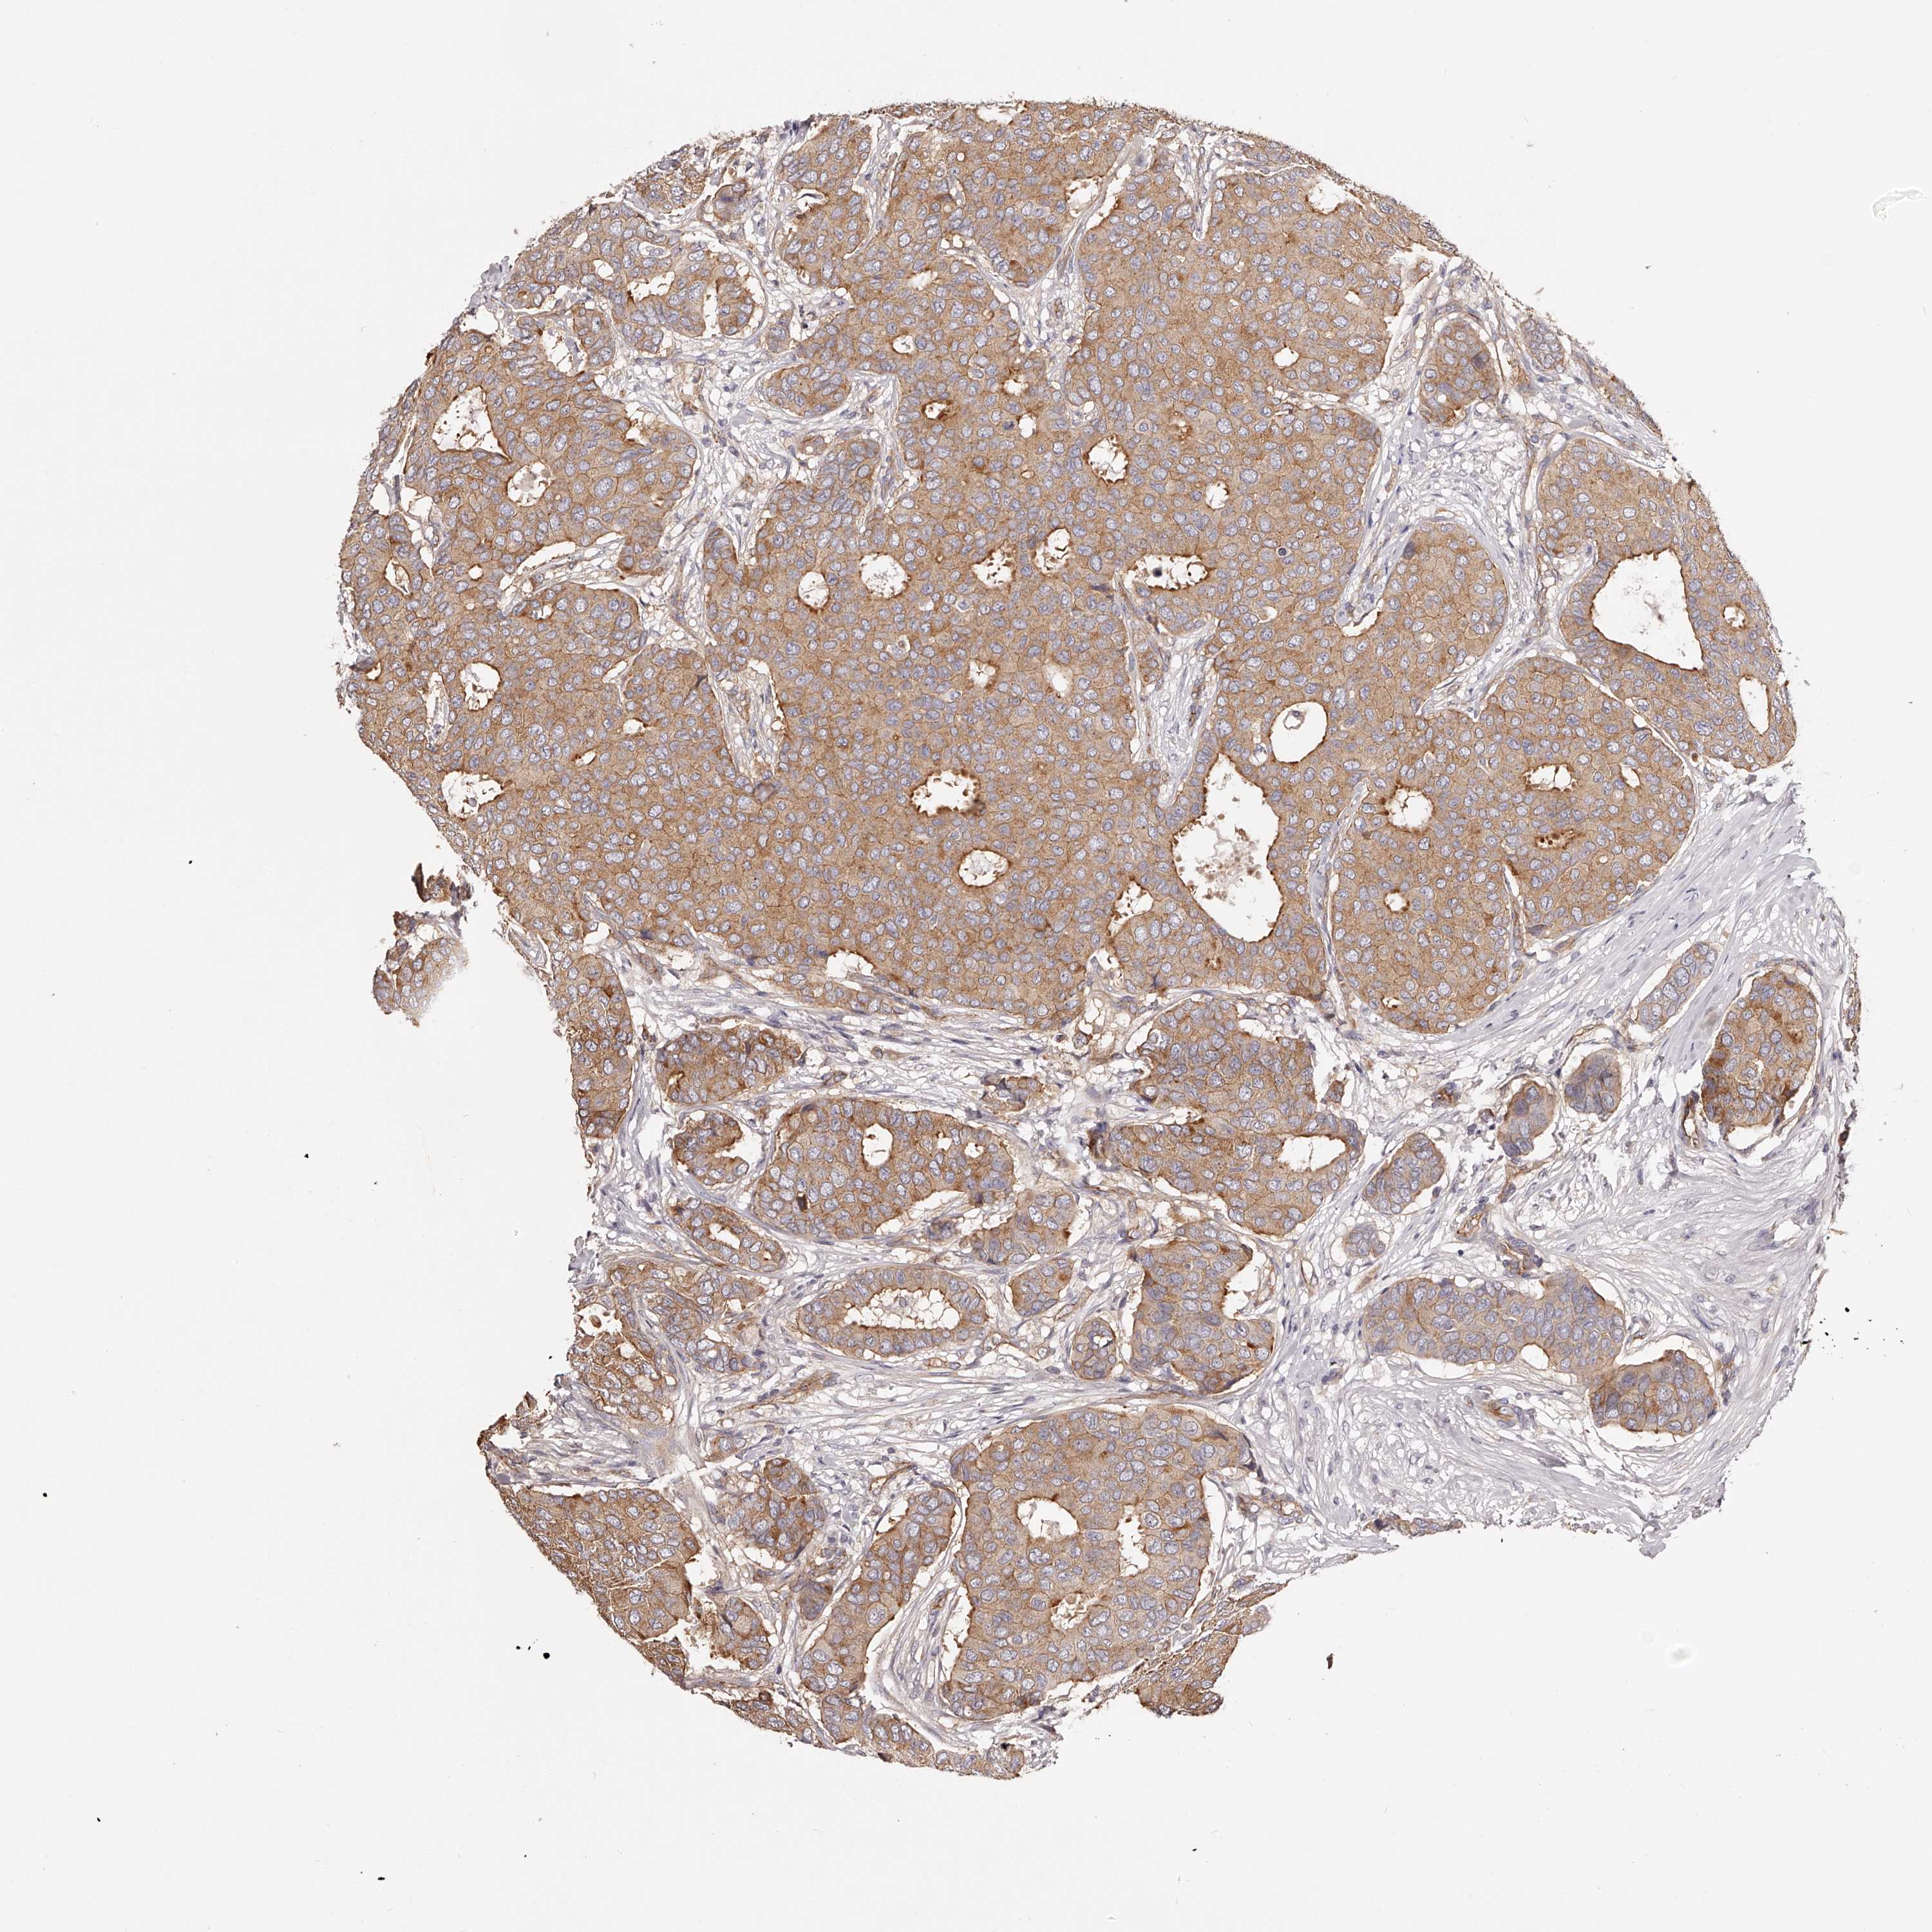

BRCA TCGA BRCA VALIDATION PROTEIN EXPRESSION

Breast cancer

Human cancer